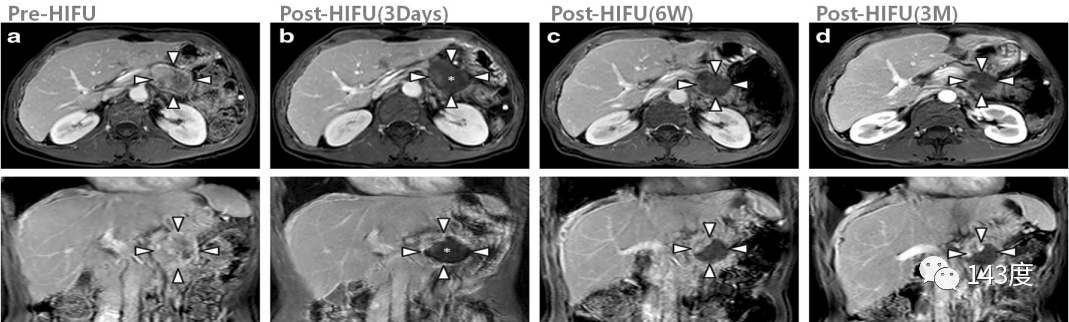

Patient: Male, 54 years old, pancreatic cancer

Pain completely relieved within 2 days after HIFU (high-intensity focused ultrasound) treatment. The tumor shrank by 62.6% at 6 weeks, 90.1% at 3 months, and CA199 levels returned to normal at 12 months.

Pancreatic Cancer Treatment Case 4:

Patient: Female, 57 years old, pancreatic cancer

Tumor necrosis occurred 3 days after HIFU treatment. The tumor shrank by 28.7% at 6 weeks, 66% at 3 months, and pain was completely relieved.